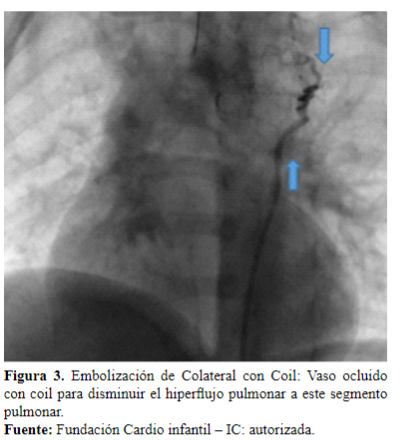

Realizado el diagnóstico, continúa la fase intervencionista; en cateterismo se realiza una embolización de colaterales, se canaliza la colateral superior izquierda que nutre el mediastino superior (Figura 2), la cual se emboliza con coil de Gianturco 38-4-3, resultando en un procedimiento exitoso y sin complicaciones, con evidencia de disminución del flujo sanguíneo de este segmento pulmonar (Figura 3).